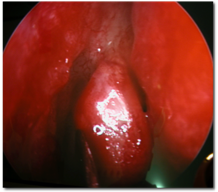

![]() |

| Endonasal DCR | |